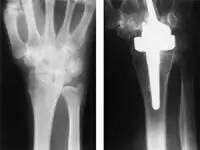

X线:腕骨关节炎的术前(左),腕关节置换术中使用了两部分组成的金属组件和聚乙烯垫片(右)。